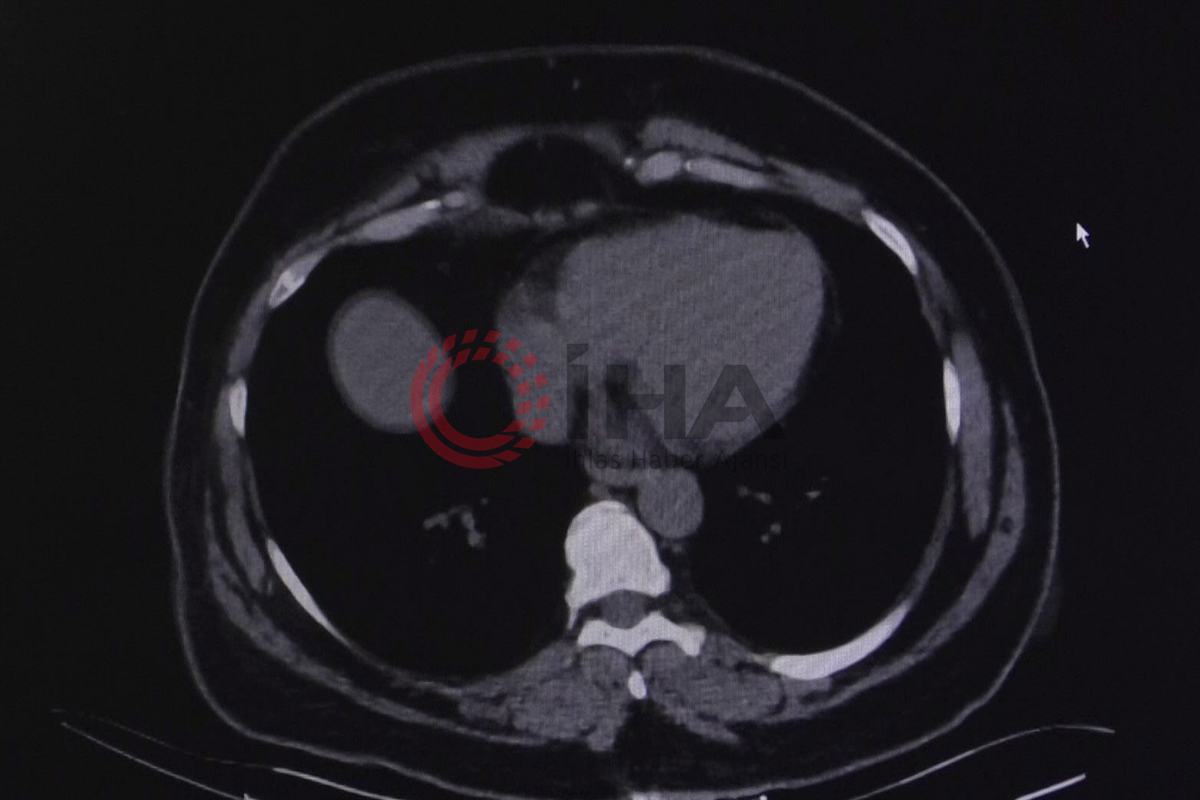

Havaların soğumasıyla birlikte üst solunum yolu hastalıklarında artış yaşanıyor. Bu durumun özellikle KOAH (Kronik Obstrüktif Akciğer Hastalığı) ve solunum rahatsızlığı bulunan vatandaşlar için farklı etkiler oluşturduğuna dikkat çekiliyor. Yedikule Göğüs Hastalıkları ve Göğüs Cerrahisi Eğitim Araştırma Hastanesi’nden Göğüs Hastalıkları Uzmanı Doç. Dr. Seda Tural Önür de hastalığa ilişkin açıklamalarda bulundu. Doç. Dr. Seda Tural Önür, kış aylarında atakların arttığına dikkat çekerken vatandaşların şikayetlerini sigaraya bağlayarak doktora geç başvurduğuna vurgu yaptı.

KOAH’ın tanı ve tedavisinin konulmaması durumunda ölüme neden olduğuna dikkat çeken Doç. Dr. Seda Tural Önür, “En sık 3. ölüm nedeni olarak KOAH tanımlamıştır. Dünyada ölümlerin yüzde 5 buçuğundan KOAH sorumludur. Bu hastalık ataklarla seyreden bir hastalıktır her atak hastalığın daha da ilerlemesine, bu sebeple hastalığın ataklarının da takiplerle, kontrol altına alınması ve önlenmesi son derece önemlidir. İlerleyici bir hastalık olduğu gibi önlenebilir bir hastalıktır. Özellikle kış aylarında daha sık olarak bu hastalığın tanısının konduğunu, ataklarla karşımıza gelen hastalarla beraber görebiliyoruz. Ev içi ve dış hava kirliliğinin kullanılan yakıtlarla beraber artması özellikle kış dönemlerinde atakların artmasına ve hastaların daha çok hastaneye başvurmasına ve ölümle seyreden sonuçlara neden olabilmektedir. Yine gribal enfeksiyonlar, kış aylarında üst hava yolları enfeksiyonları atak sıklığını arttırdığı için bu hastalarda ciddi seyredebilmektedir. Dünya Sağlık Örgütü de o yüzden bu hastalarda grip ve zatürre aşısının mutlaka yapılmasını ve enfeksiyonlardan bu hastaların öncelikli olarak korunması gerektiğini, atakları koruduğundan dolayı mutlaka önermektedir. Şikayetlerini sigara kullanımına bağlayarak sağlık kuruluşlarına daha geç başvurabiliyorlar. İlerleyen dönemlerinde de hastalık solunum yetmezliği tablosuyla beraber çeşitli oksijen cihazlarına bağlı kalma durumları dahi söz konusu olabiliyor” ifadelerini kullandı.